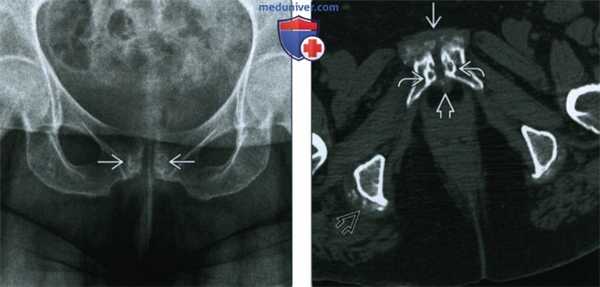

(Слева) Рентгенография в ПЗ проекции: определяется аномальное лобковое сочленение с субхондральным склерозом и субхондральными кистами. Разрушение копи отсутствует.

(Справа) Бесконтрастная КТ, аксиальный срез: хорошо видны изменения при болезни отложения кристаллов. Изменения включают околосуставную минерализацию, образование субхондральных кист и гипертрофию капсулы. Схожие изменения наблюдаются в правой подвздошно-ягодичной сумке.